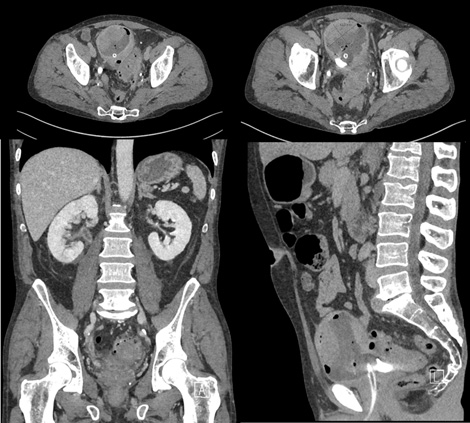

‘Case of the month from University Hospital Bern, Switzerland: bladder tumour with extreme leucocytosis

Amir Naiem, Gallus Beatus Ineichen, Antonio Rodriguez Calero, George N. Thalmann